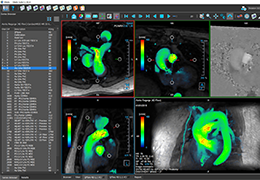

ANYTHINK 经导管主动脉瓣膜置换术分析系统